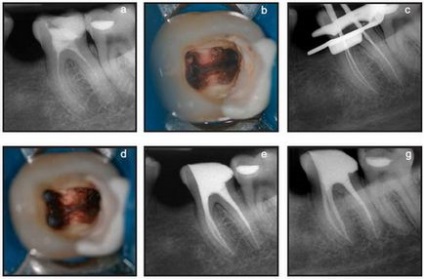

Klinikai eset №5.

a, b) az első moláris a mandibula bal indikációk kezelésére endodontiche-ég. c, d) meghatározása az üzemi hossz. A töltelék anyagot eltávolítjuk a csatornák útján eszközök Mtwo R. master file Mtwo 35.04. e, g) kitöltése gyökércsatornák (meg a különböző előrejelzések).

Klinikai eset №6.

a) a második kisőrlő felső állkapocs jelzések endodonciai kezelés.

b) eltávolítása után a töltőanyag keresztül Mtwo R fájlok apikális preparátumot végzett két további eszközöket Mtwo egy méret # 40. Kitöltése a gyökérkezelés rendszer igazolja komplex anatómiája a csúcsi része a gyökér.